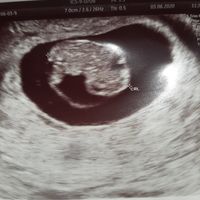

14Buenas tardes chicas, He sido madre por primera vez a principios de diciembre de 2022, con 39 años cumplidos en septiembre. Me quedé embarazada con 38 años sin problemas. Me planteo darle un hermano/a...